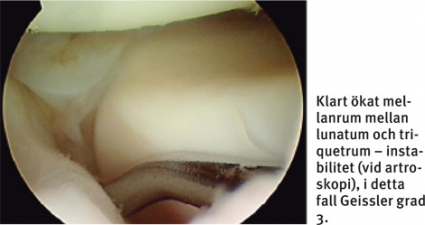

Artroskopi är etablerad standardmetod i diagnostiken. Den ger en direkt uppfattning om graden av instabilitet, vilket MR inte kan ge. Artroskopi ska ske genom portaler i både radiokarpal- och midkarpallederna [9]. Vid artroskopin görs – förutom inspektion – palpation och provokation med hjälp av artroskopihake. Instabilitet i lederna kan då graderas från midkarpala vyn. Vanligaste klassifikation som underlag för val av behandling är Geisslers.

Stabilitetstest i röntgengenomlysning, direkt preoperativt, kan också vara av värde. TFCC-skada är framför allt en klinisk diagnos, där artroskopi mer används för att bedöma skadans utbredning och värdera förutsättningarna för reparation av ligamenten. Differentialdiagnostiskt har artroskopin här dock stort värde för att se andra eventuella ligamentskador och samtidiga broskskador.